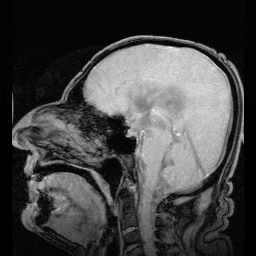

脑脊液会从侧脑室出发,进入第三脑室,再到第四脑室。从第四脑室开始,一部分脑脊液会进入脊髓中,而还有很大一部分会进入蛛网膜中,最终汇集到耳部的外淋巴系统,排出大脑。今年2月,在一项发表于《自然》(Nature)的研究中,美国华盛顿大学医学院的科学家发现,人在睡眠阶段时,大量神经元会一起活动,产生频率约40Hz的γ波,促进脑脊液进入脑组织,并推动脑组织中携带废弃物的间质液排出,进而清除对大脑有害的各种废弃物。

而脑脊液是否会漏出去,和蛛网膜外侧的硬脑膜的完整性密切相关。硬脑膜厚且致密,并且弹性很小。在人脑中,有两个大的、特殊的硬脑膜组织,分别是将左右半球分开、形态像镰刀的“大脑镰”,以及将大脑和小脑分开的“小脑幕”,它们对于维持人脑结构至关重要。如果硬脑膜因为外伤而损伤,或者受遗传因素出现了发育缺陷的话,就很有可能出现脑子“漏水”的情况。

而想要长久地解决这一问题,最有效的办法无疑是找到脑脊液泄漏的地方,然后将其堵上。例如,文章开头那名45岁的男性在接受检查时,医生发现他右脑的中颅窝中存在一个不正常的、8毫米×5毫米左右的骨缺口(里面的脑膜也受损了)。而他的脑脊液正是从这里漏出后,进入了中耳。在手术中,医生使用一种“塞子”结构(包括软骨,筋膜和骨泥),在头骨外侧给他打了一个补丁。不过,后期随访时,医生发现他虽然右脑好了,但左脑又出现了一个骨缺口,他们又以同样的方式,给他打上了一个新的补丁。

脑脊液漏曾被认为相对罕见,科学家估计每年每10万人中会有5人出现这种情况。随着对脑脊液漏了解的逐步深入,以及成像技术的进步,医生正在发现越来越多的脑脊液漏病例。这种情况更常出现在中年人中,并且女性患者比男性患者更常见。现今的影像学检查正在帮助对这种疾病做出诊断,例如对整个大脑或脊柱的核磁共振扫描(MRI)等。